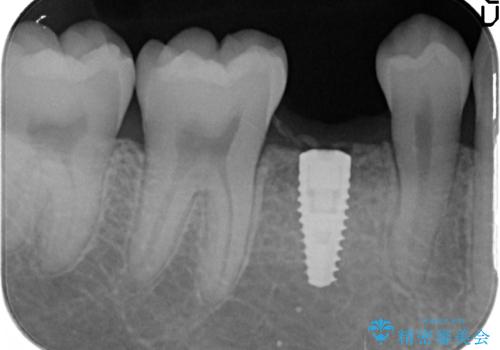

そのため、5番目のインプラントと、7番目の骨整形を同時に行い、整形で取れた7番目の骨をインプラント周囲に移植し、骨を増やすことにしました。

元々乳歯が残っていた場所であり、骨はたくさんあったため、インプラントを入れるのにそこまで支障はありませんでした。

ただし、奥歯の骨外科治療を同時に行うことで、同時についでに自分の骨を移植できるタイミングだったため行っておきました。